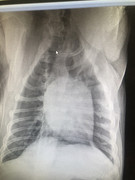

Сегодня собака была на обследовании - диагноз: эндометрит и опухоль.

Операция может дать шанс на жизнь Белке! Но делать ее нужно срочно!